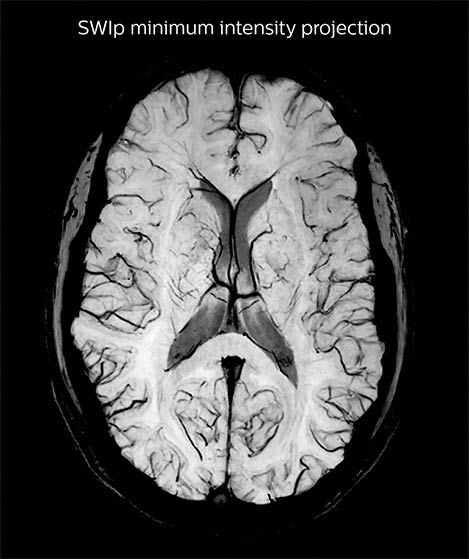

A SWIp image (left) is used to visualize veins in cortical and sub-cortical areas. Using in-house reconstruction techniques, a vascular density map is obtained in individual subjects and averaged over a population (right). Areas in red/green represent areas with dense venous vascularization. The lab uses such images to correct fMRI (BOLD) activation maps in order to minimize false positives.